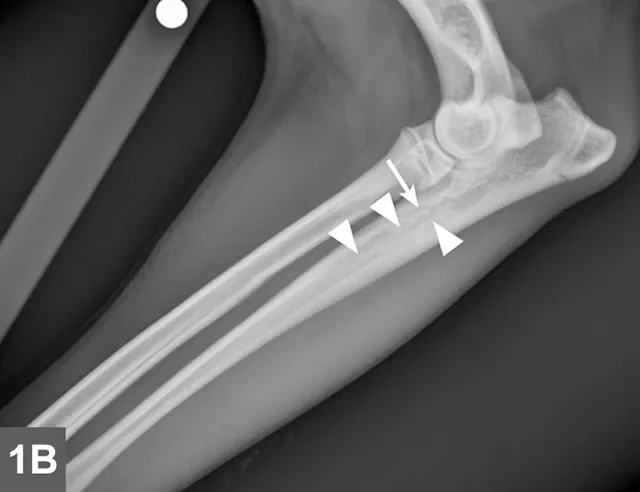

Radiographic signs of panosteitis frequently lag days to weeks behind clinical signs.1,3 The earliest radiographic sign of panosteitis is a decrease in opacity around the nutrient foramen. Later signs include an increase in mineral opacity within the medullary canal of long bones and loss of the normal trabecular bone pattern (Figure 1). Smooth periosteal and endosteal new bone may also be seen in more severe cases (Figure 2). Radiographs of the affected limb may be compared with those of the contralateral limb to assist in diagnosis. Nuclear scintigraphy may assist in diagnosis in cases in which radiographic changes have not yet developed.4

Lateral radiographic projections of the femur (A) and ulna (B, next slide) in dogs with early signs of panosteitis. Note the radiolucency around the nutrient foramen (arrows) and increased opacity within the medullary canal (arrowheads) in both cases.